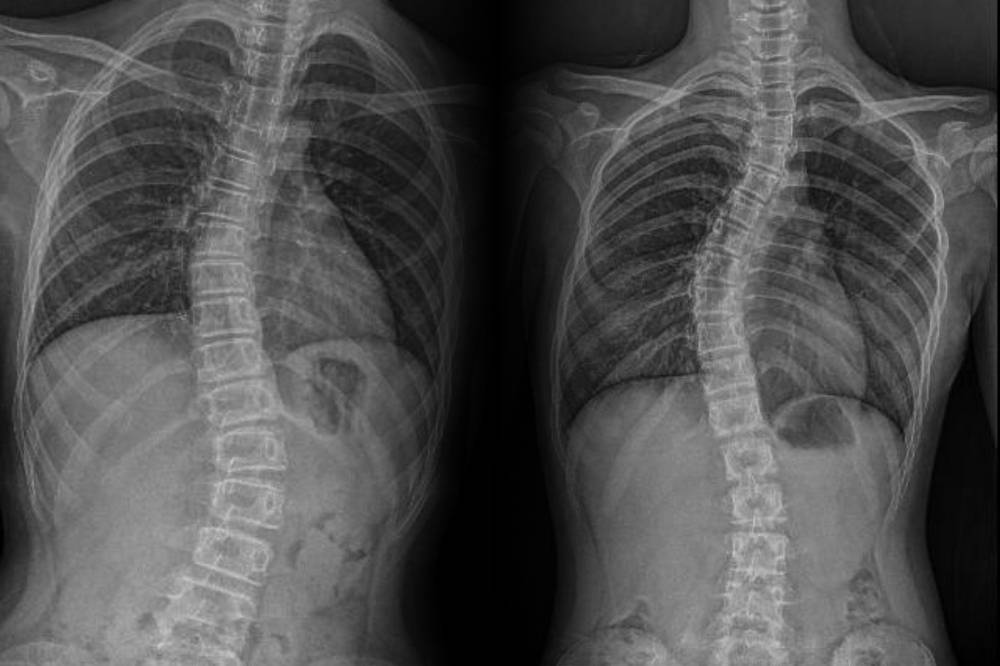

Diagnosis typically begins with a clinical evaluation and spinal X-rays to assess curvature type and severity. For patients whose spines have stopped growing, observation combined with physiotherapy and strength training may be sufficient.

“A simple spinal radiograph is often all that is needed to determine whether scoliosis is present. If we detect it early, we can plan the right course of action. Whether it is monitoring, bracing or in some cases, surgical correction.